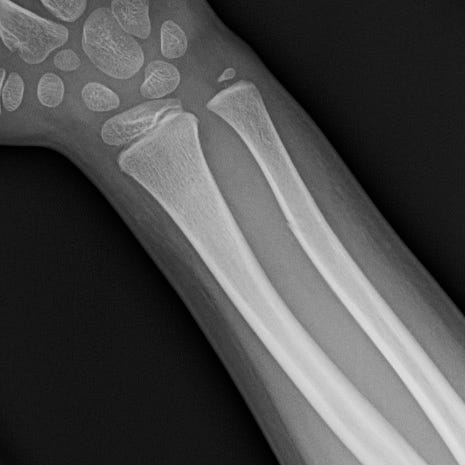

Greenstick fractures are incomplete fractures of long bones of children that result from forces perpendicular to the axis of the bone. Young children have more compliant long bones that have a greater tendency to bow and bend under stress rather than fracture. Greenstick fractures consist of a complete fracture or cortical disruption of the bone opposite the impacted side while the ipsilateral cortex remains intact. Treatment consists of closed reduction and immobilization.

Greenstick fracture. Distal radial and ulnar bowing with dorsal angulation of the distal radial fragment and incomplete disruption of the cortices.